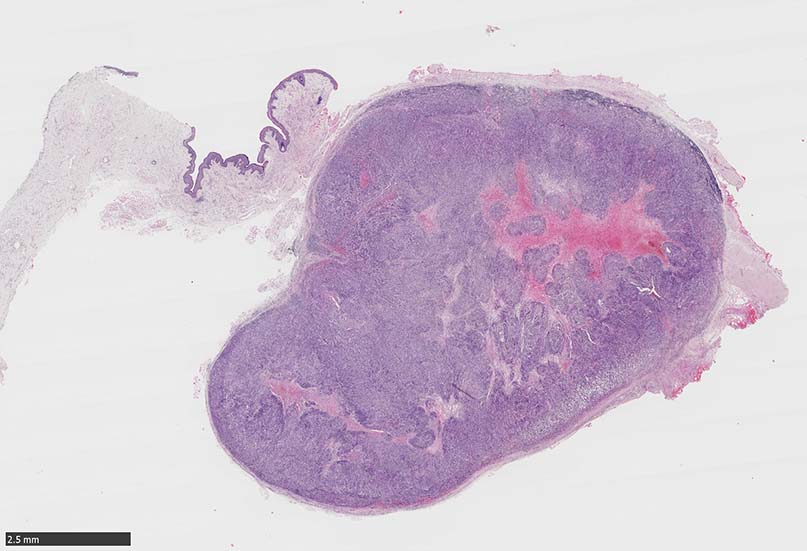

SPS244-Case02 項部皮下腫瘤 70歳代女性

潰瘍びらんはない割面loupe像